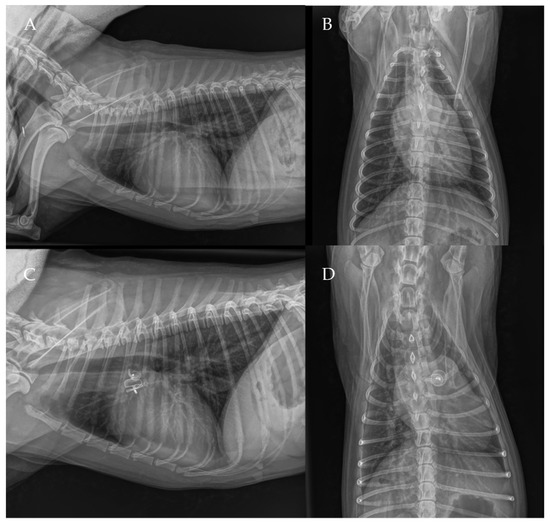

The thoracic radiographs performed before and just after the procedure showed a reduction in the cardiac silhouette as well as significant reduction of the over-circulation vascular pattern for all dogs (Figure 8, Figure 9, Figure 10, Figure 11 and Figure 12).

Figure 9. Pre-procedure (A,B) and post-procedure (C,D) left lateral and dorso-ventral thoracic radiographs of Case 2. L: left; R: right.